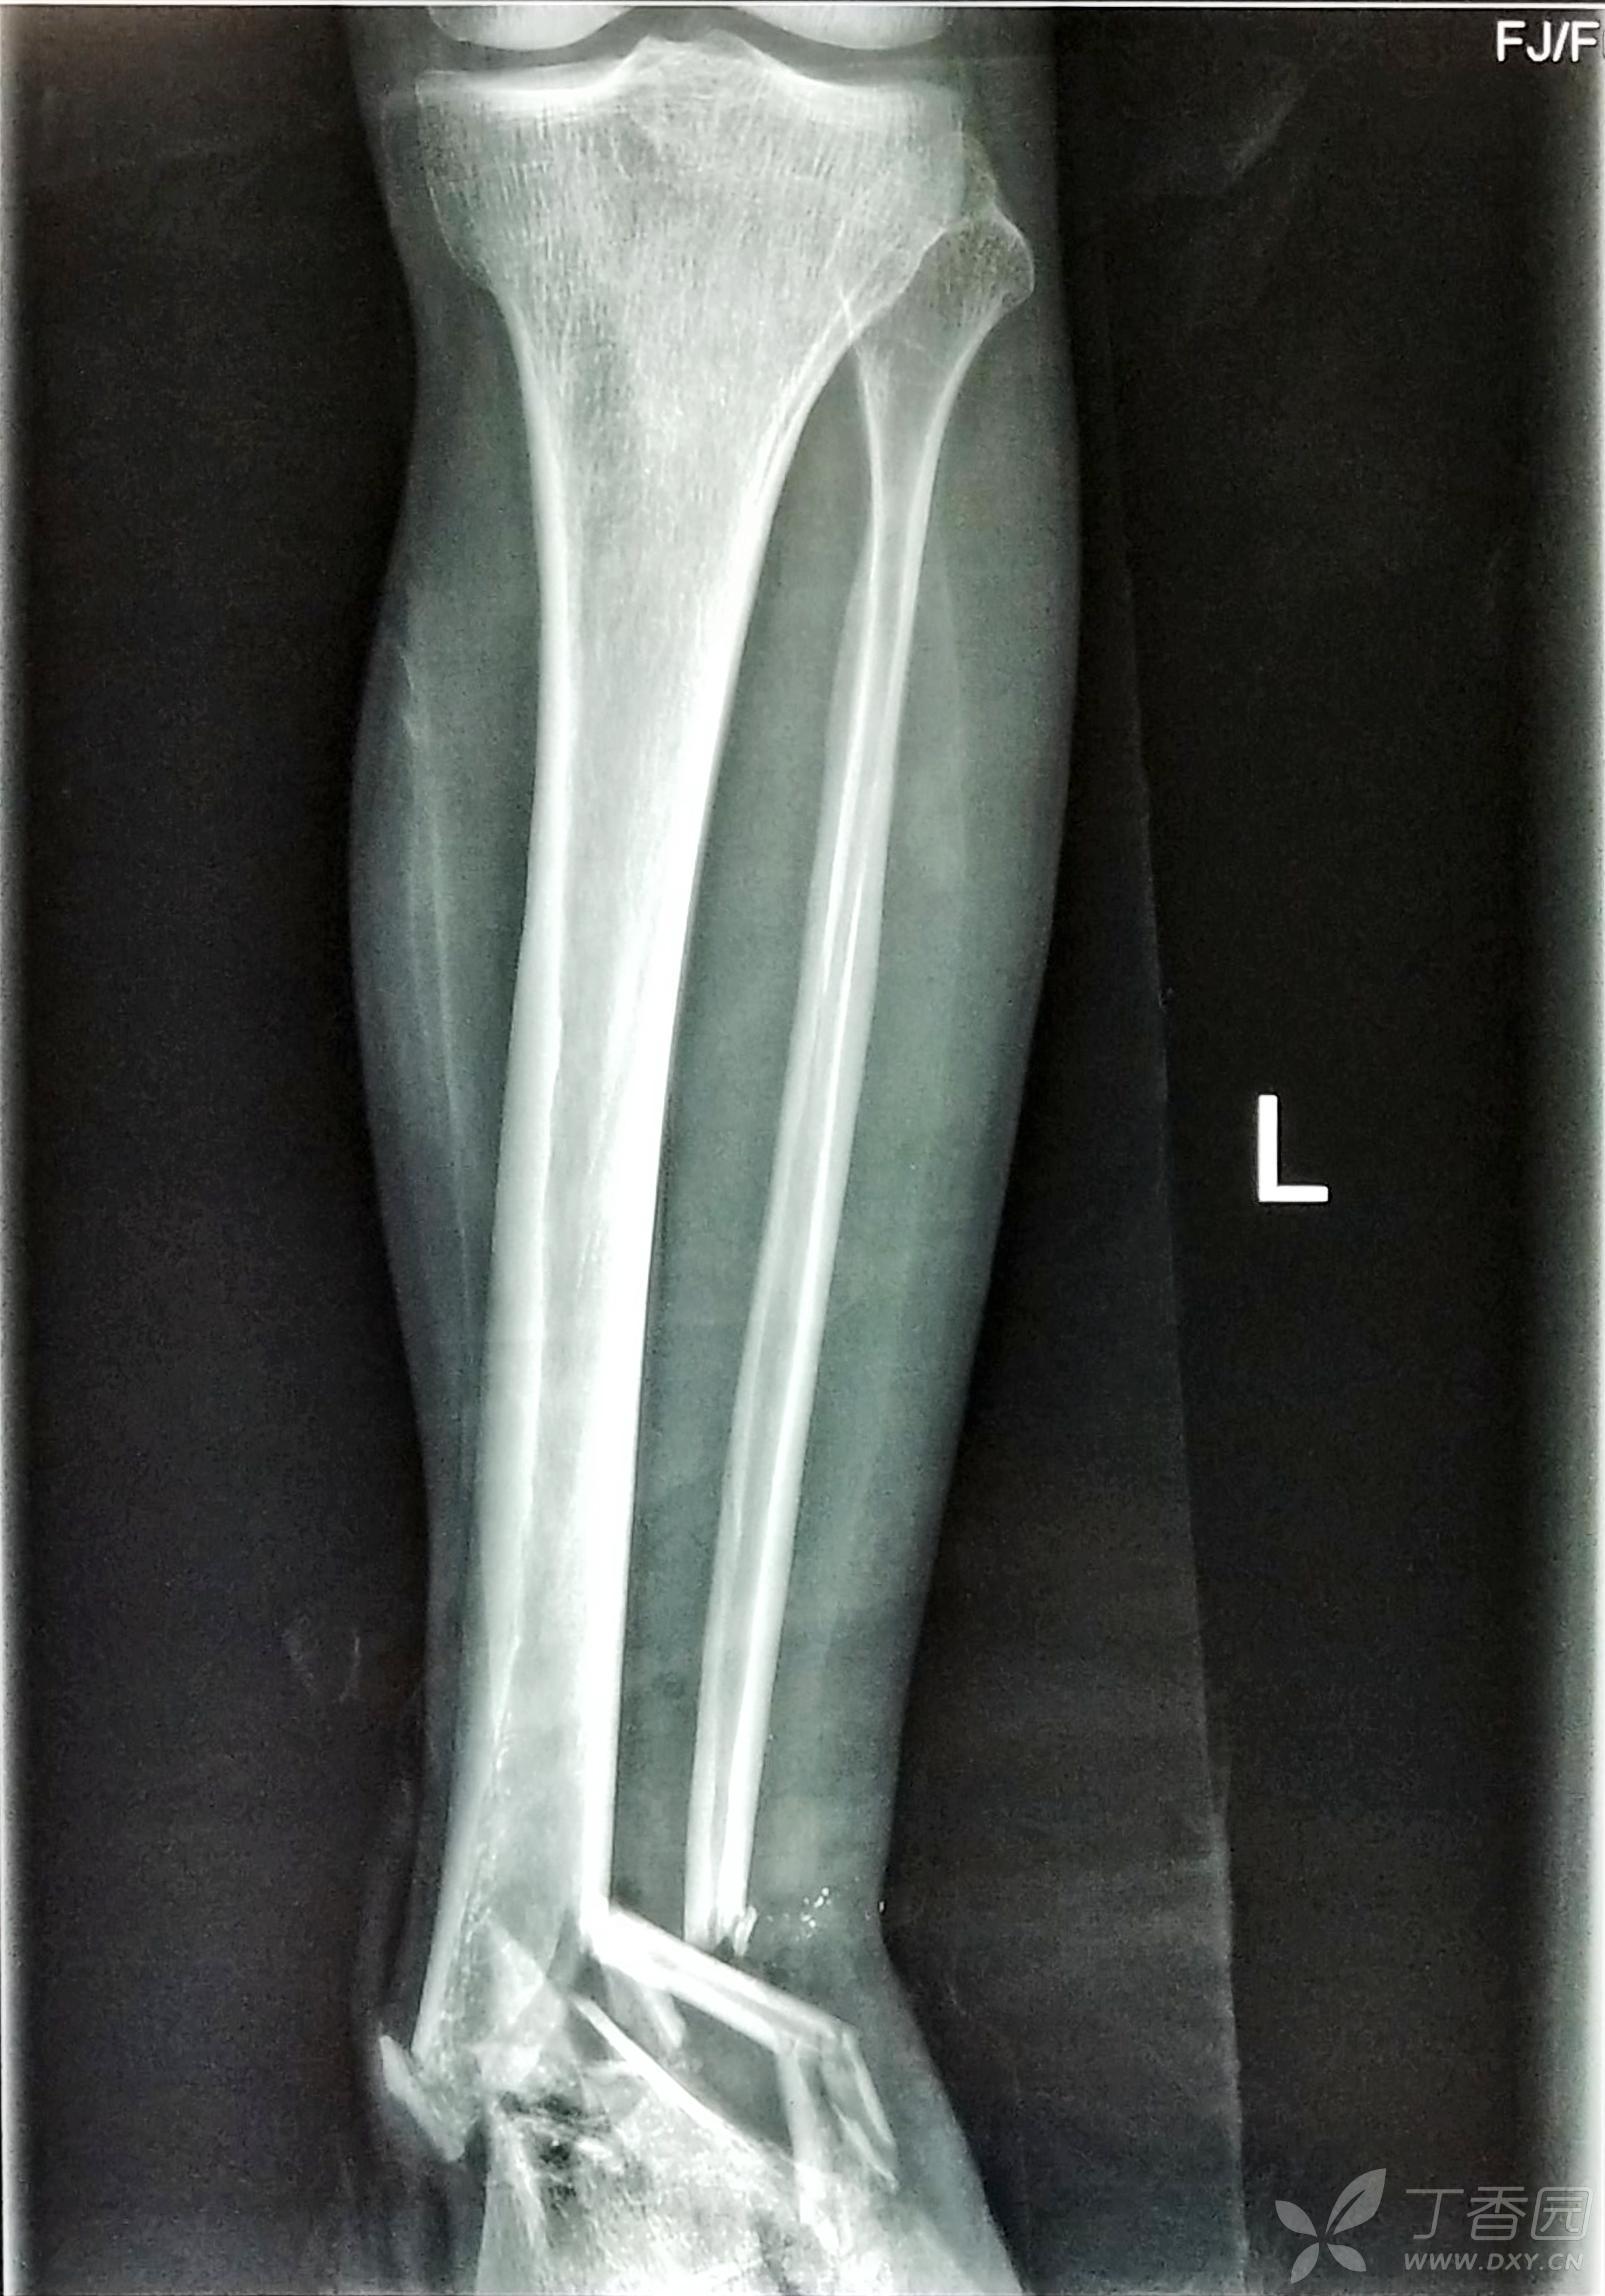

胫腓骨骨折 骨科专业讨论版 丁香园论坛

一例胫腓骨骨折髓内钉治疗 病例中心 诊疗助手 爱爱医医学网